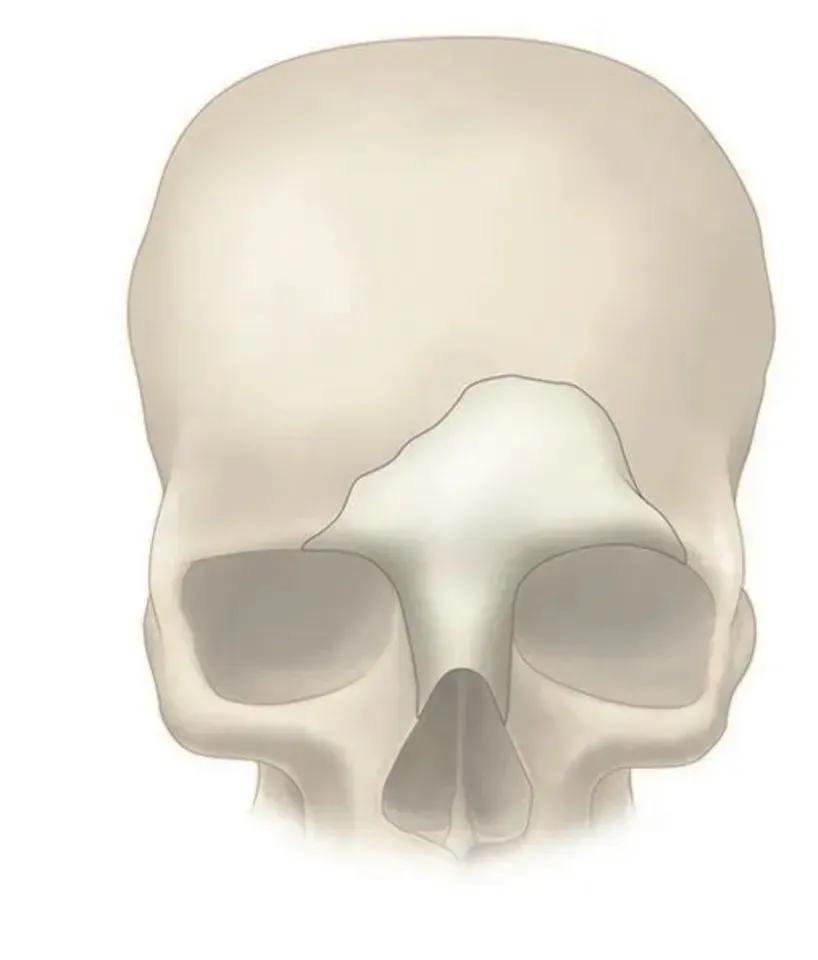

PEEK can be designed and provided in single or multiple pieces with just-fit or over-lay concept as indicated above. Additionally, this patient specific implant can be reliably fixated using cranial fixation systems.

Perfect Contour Reconstruction

Precisely match the natural contour and convenient to implant. CAD/CAM technology allows to restore the defect models and reconstruct the natural contour of the brain.